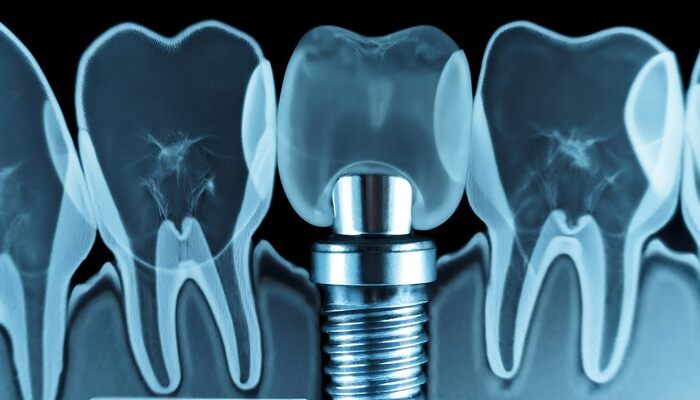

下顎では下歯槽神経、上顎では上顎洞の貫通リスク、また粘膜や歯槽骨の状態によっては、ドリル操作による損傷や出血、術後の腫れなどが起こる可能性があります。こうした偶発症の多くは、CTなどの画像診断により事前に予測・回避できるケースもありますが、骨の密度や厚み、個々の解剖学的差異などにより完全な予防は困難なこともあります。

神経損傷のリスクは、主に骨の厚みや形状を把握しきれていないままインプラントを埋入した場合や、術前の診断で神経管との距離を正確に評価していない場合に高まります。CTによる三次元的な骨構造の把握と、下歯槽神経の走行位置の把握は必須であり、術前の画像診断が偶発症予防において極めて重要です。

インプラント治療において診断不足は偶発症の最も大きな要因のひとつです。歯槽骨の厚みや高さ、下顎の神経の走行、上顎洞の深さなどを正確に把握できていない場合、予期せぬ合併症や損傷が起こりやすくなります。特にCTを用いた三次元画像診断を省略して二次元的なレントゲン画像だけに頼った場合、骨密度や構造の詳細が読み取れず、埋入位置の誤りに繋がるリスクが高まります。

インプラント手術において偶発症を回避するためには、術前診断の精度が結果を大きく左右します。特に三次元的な情報を得られるCT画像の活用は、骨の状態を正確に評価するうえで欠かせません。骨の形態や厚み、神経や血管の走行位置、上顎洞の深さなどを正確に把握することで、ドリルの穿孔位置や角度を的確に計画できます。

二次元のレントゲン画像では見落としがちな部分も、CT画像であれば断層レベルで確認できるため、より安全な埋入が可能になります。加えて、診断ソフトを活用したシミュレーション機能により、仮想手術を事前に行うことで術中のトラブルを回避する効果も期待できます。